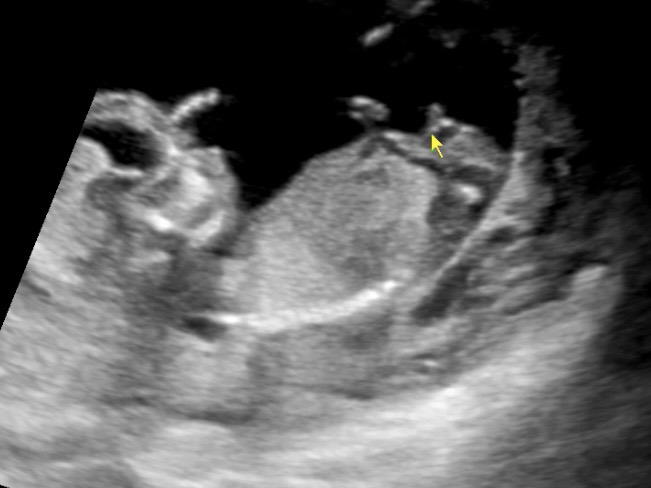

12주4일 초음파 사진입니다! 각도법 어려워서 잘 모르겠지만 제 눈엔 너무 아들 같은데 어떤가요? 둘째 딸이길 간절히 소망해왔는데.. 각도법 고수님들 도와주세요ㅠㅠ 부탁드립니당